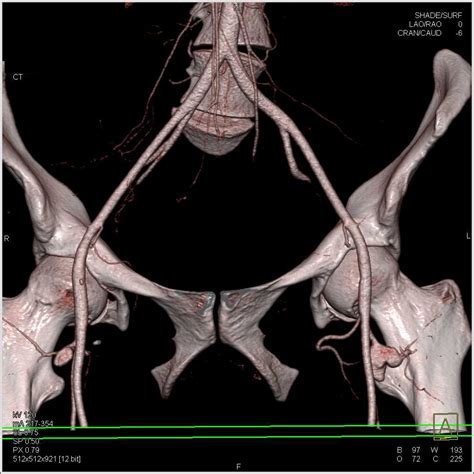

Physicians use various imaging techniques to confirm the presence of a femoral artery aneurysm and assess its size, location, and potential for complications. Accurate diagnosis is vital for planning the appropriate treatment path.

CT Angiography (CTA) Provides highly detailed cross-sectional images to map the vascular anatomy and plan for potential surgery.